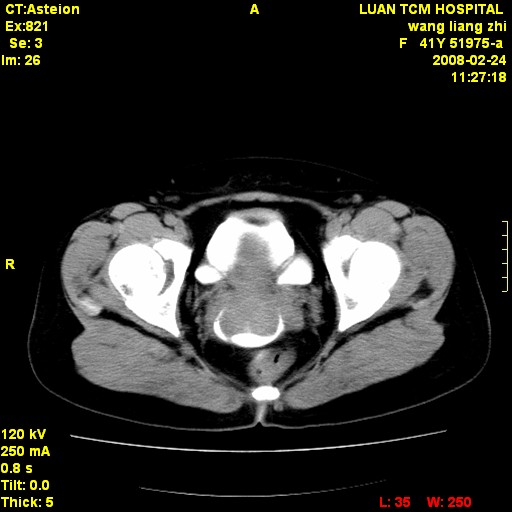

以下是引用dyqct在2009-8-23 16:17:00的发言:[br]考虑:1、造影剂进入腹腔、结肠旁沟、肝周;[br] 2、子宫明显增大(腺肌增生症?);[br] 3、膀胱显影是由于造影剂吸收后经肾分泌进入膀胱的;[br] 4、建议mri检查子宫。